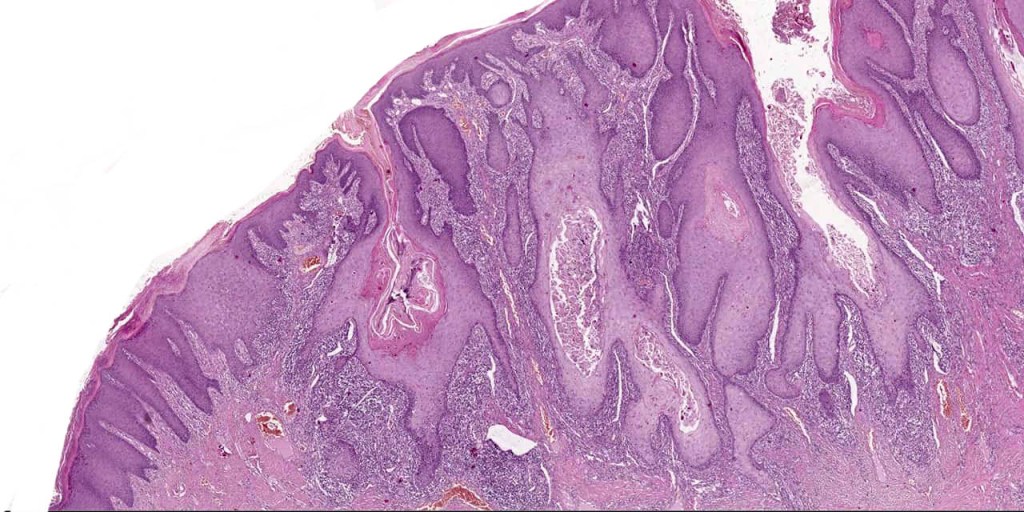

•Often massive hyperkeratosis

•Epidermal verrucous hyperplasia

•Deeply penetrating bulbous processes with a pushing rather than infiltrating lower border

Verrucuous carcinoma must be distinguished from a viral wart, pseudoepitheliomatous hyperplasia and well differentiated squamous carcinoma. This can be very difficult if only superficial biopsies are available for study. Distinction from a plantar wart is sometimes very problematical since some verrucous carcinomas are associated with HPV infection. Well differentiated squamous carcinoma has an infiltrating rather than a pushing lower border. Clinicopathological correlation is essential in problematical cases.